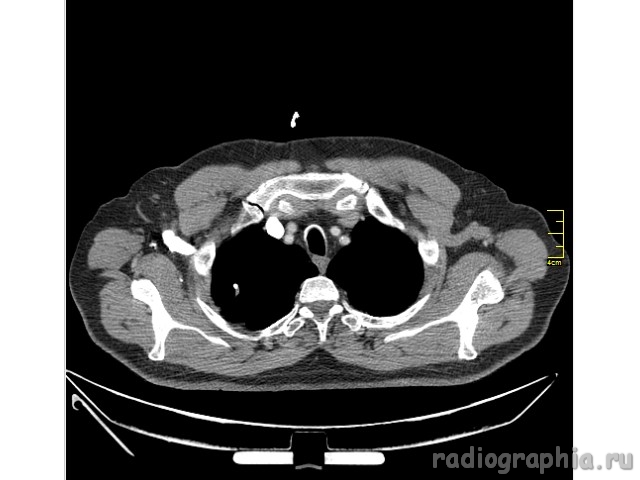

Одиночный узел правого лёгкого.

На рутинном снимке ОГК, был выявлен одиночный узел; по протоколу выполнили КТ. Какое было бы ваше заключение; и как бы Вы поступили если у вас нет возможности выполнять КТ?